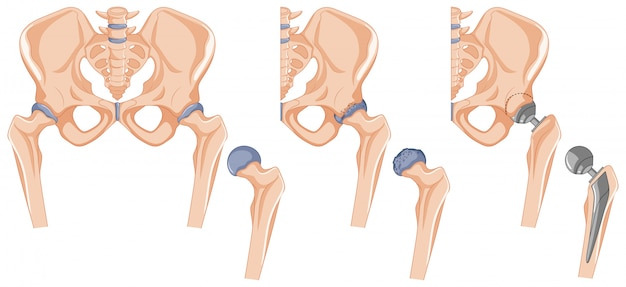

- 전문가의 도움: 심한 골반 틀어짐의 경우, 전문가의 도움을 받는 것이 좋습니다.